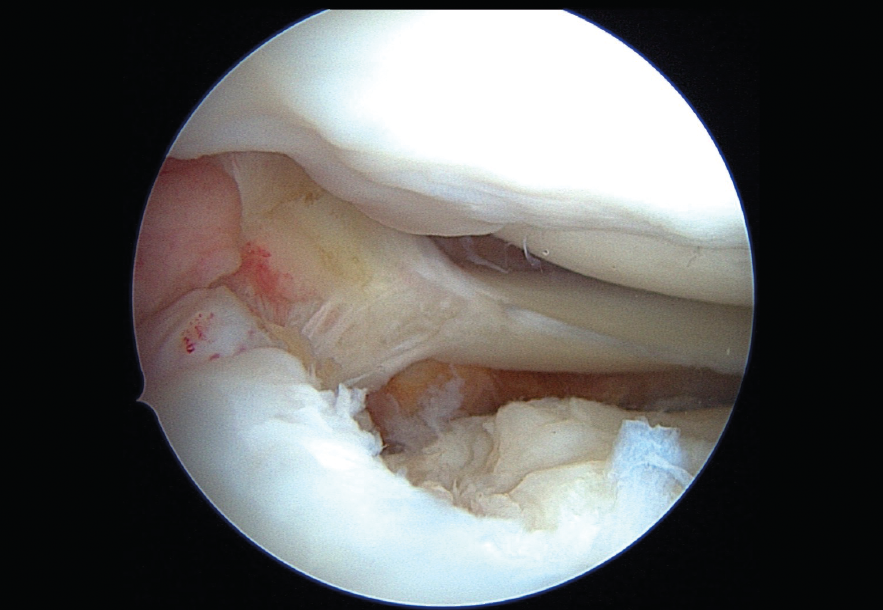

La raíz meniscal está relacionada con la distribución de cargas axiales en forma circunferencial, pero tiene también una importante función como coadyuvante de la estabilidad rotacional de la rodilla. Así, su lesión puede causar un aumento de presiones equiparable a una meniscectomía. Esta se presenta en el 7 al 15% de los casos de rotura del ligamento cruzado anterior (LCA), condicionando inestabilidad residual traslacional de la tibia y aumentando la incidencia de cirugía de revisión. Por ello, son imprescindibles su diagnóstico y reparación. En esta fotografía vemos una lesión de la raíz posterior del menisco externo en la rodilla izquierda de un deportista sometido a cirugía de revisión del LCA.